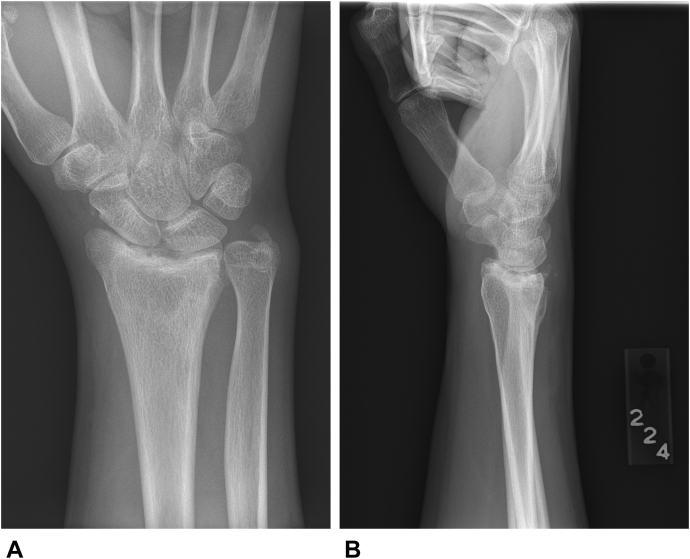

The patient presented at age 16, approximately 10 months after open reduction and pin fixation of a distal radius fracture caused by falling off a horse. At the time of the initial injury, an attempt at volar plate fixation at an outside facility was aborted because of the severe comminution, and the fracture was simply fixed with Kirschner wires. Figure 1 shows the anteroposterior and lateral views at the time of the initial procedure. The patient was immobilized for approximately 8 weeks, and the wires were removed. He was referred to physical therapy but continued to have ongoing problems, with increasing pain and lack of motion. At 10 months postinjury he was referred to our institution.

Figure 1.

A AP view of the patient’s wrist after open reduction and fixation with Kirschner wires. B Lateral view of the patient’s wrist after open reduction and fixation with Kirschner wires. AP, anteroposterior.